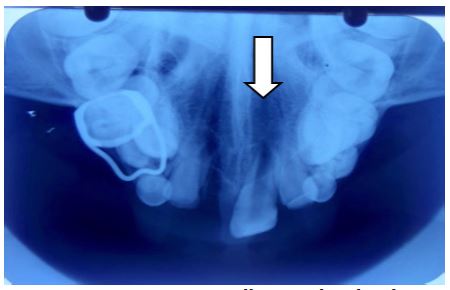

On radiographic investigation, IOPAR (Figure 3) and maxillary occlusal radiograph (Figure 4) revealed well defined radio-opacity superimposing normal radio density of right maxillary central incisor. In addition to above radiographic findings, OPG (Figure 5) also showed that the maxillary right lateral incisor was missing. After assessment of axial and coronal sections of CBCT of maxillary anterior region (Figure 6a, 6b, 6c. 6d, 6e), it was found that there was expansion and thinning of labial cortices of left maxillary central incisor. There was no radiographic evidence of root resorption of adjacent teeth. The root of right central incisor was dilacerated and curved with diffuse periapical rarefaction. At the area of maximum concavity, a well defined radio opaque mass was evident in the midline attached at CEJ of right maxillary central incisor (11) suggestive of odontome attached with the tooth. As a treatment plan, extraction of 11 along with the odontome was advised. After the surgery, the patient was called for follow-up and within a month, partial eruption of left maxiallary central incisor (21) was seen (Figures 8,9).

Figure 5: OPG shows well defined radio opacity with cortical border superimposing the radiodensity of 11. Incomplete apex w.r.t. 21,16,26,36,46, Crown with 2/3rd root formation w.r.t. 22, Crown formation with 1/3rd root formation w.r.t. 13,23, Crown completeion w.r.t. 14,17,24,25,27,33,34,43,44, ½ of crown completeion w.r.t. 15,35,45,37,47 and Radiographically missing 12.